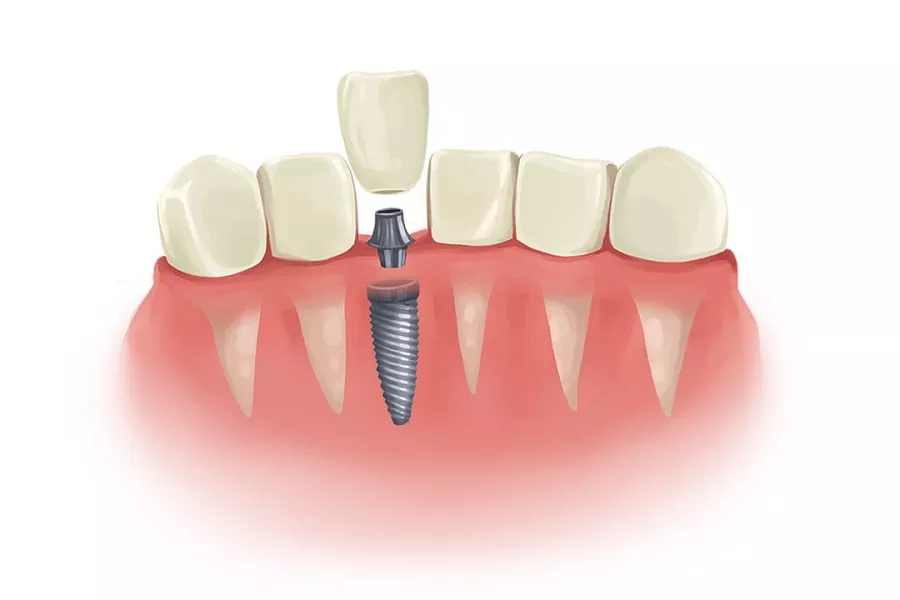

2. Implant structure The implant is also called the lower structure. Artificial dentures are also called superstructures. The implant consists of the following three parts:

Body: The part of the implant that is inserted into the human tissue. According to its implantation site, it is divided into: A. implanted in mucoperiosteal or B. implanted in soft tissue.??

Neck: The part that connects the body to the pile or abutment.??

Pile or abutment: The exposed part of the dental implant beyond the mucosa that provides support, retention and stabilization of the artificial denture of its superstructure. Two of them are rarely seen in the current production. Generally, they are directly 1 and 3, that is, 1 and 3 in the right picture, and 3 in the right picture is an artificial denture.